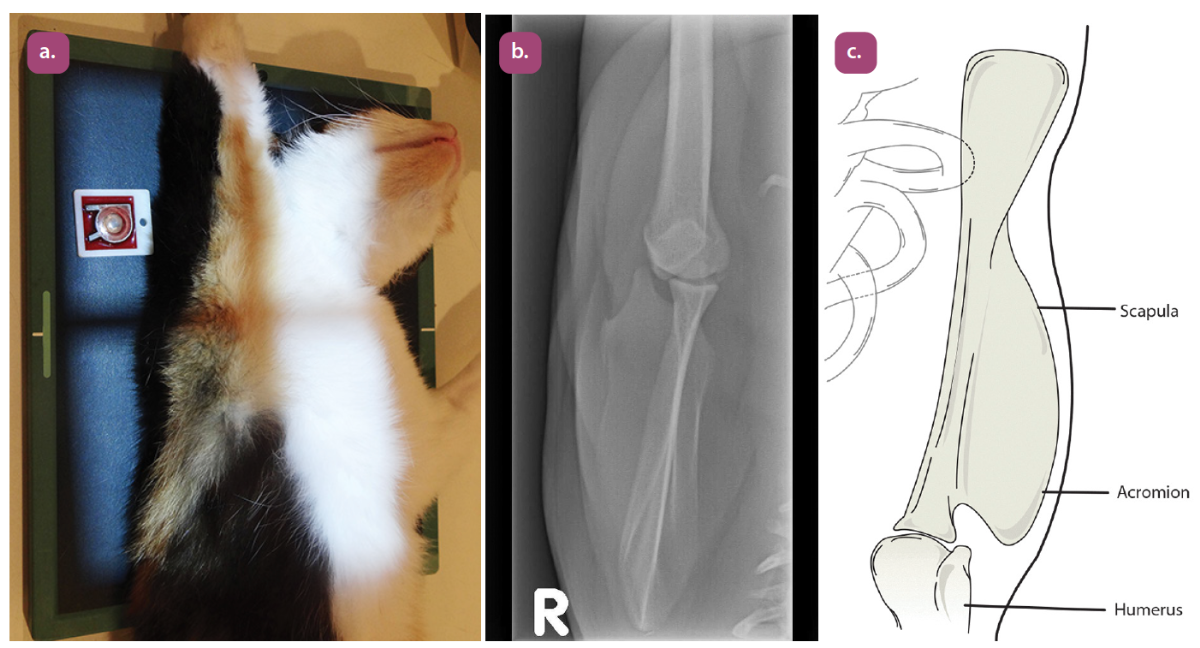

lateral projection of the humerus

caudocranial projection of the humerus

craniocaudal projection of the humerus